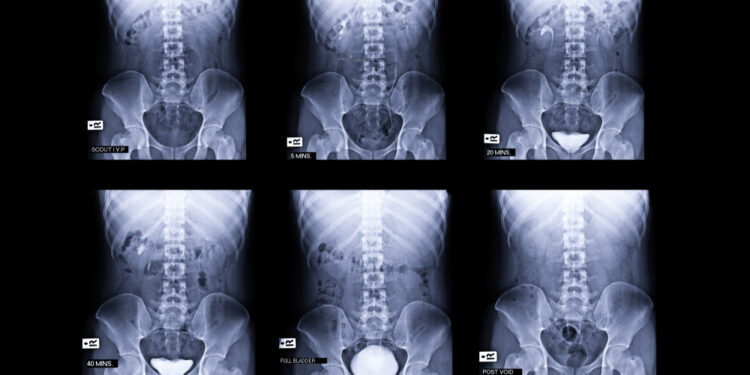

Šlapimtakis – tai plonas vamzdelis, vedantis šlapimą iš inksto į šlapimo pūslę. Kiekvienas iš mūsų turi du šlapimtakius – po vieną iš kiekvieno inksto. Viršutinė šlapimtakių dalis eina pilvo srityje, o apatinė – dubenyje.

Vidutinio suaugusio žmogaus šlapimtakio ilgis svyruoja nuo 25 iki 30 centimetrų. Šios struktūros sienelės yra storos: jos sudarytos iš jungiamojo audinio, lygiųjų raumenų sluoksnio ir gleivinės dangalo, kurie leidžia šlapimtakiui susitraukinėti bei pernešti šlapimą į pūslę.

- Obstrukcija ties inksto ir šlapimtakio jungtimi. Kai užsikemša vieta, kuri jungia inkstą su šlapimtakiu, šlapimas negali nutekėti iš inksto.

- Užsikimšimas ties šlapimtakio ir pūslės jungtimi. Ši kliūtis atsiranda toje vietoje, kur susijungia šlapimtakis ir šlapimo pūslė.

Kai šlapimas negali laisvai pratekėti pro šlapimtakį, gresia įvairios komplikacijos, tokios kaip inkstų uždegimas, dalinis ar visiškas inkstų veiklos sutrikimas, taip pat gali formuotis inkstų akmenys.